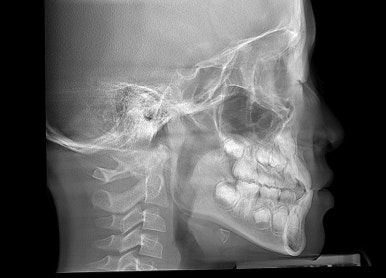

옆모습 X-ray가 매우 중요합니다.

위-아래턱의 뼈 크기, 비율 등을 정확히 계측해서 뼈의 성장 양상을 정확히 파악해야 됩니다.

이번 환자분은 뼈 자체가 주걱턱 양상이어서 뼈를 성장 시켜주는 페이스마스크를 사용하기로 했습니다.